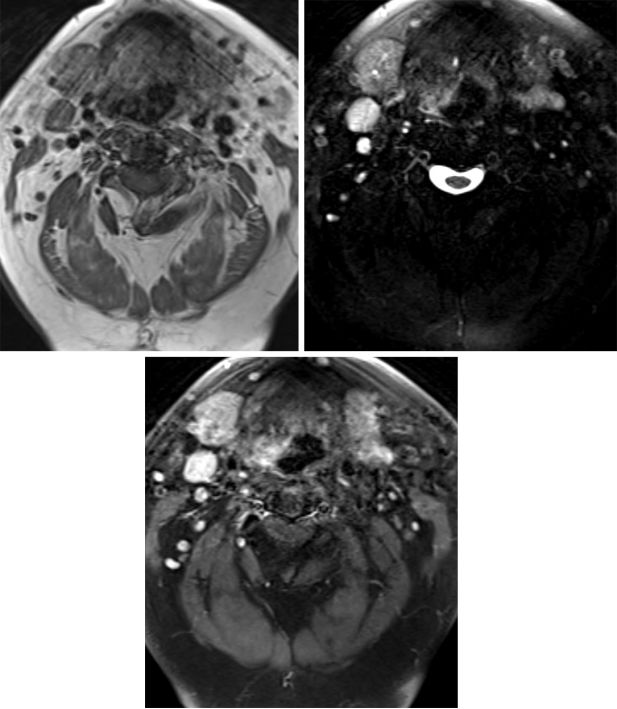

图1:T1加权(左上)提示随颈动脉间隙走行的迷走神经存在一个低信号的占位病变,这种损伤很容易被误诊为淋巴结。与其他副交感神经节瘤相同,这些损伤在T2加权相显示为典型的“椒盐征”,即混杂的血管流空高信号(右上),并且在T1增强加权相表现为持续增强。

“椒盐征”为MRI特征性表现

T1高信号“盐”是由于亚急性出血,低信号的“椒”是由于动脉血管流空现象(在大肿瘤中更常见)

T1加权相:呈不均一信号,可伴有亚急性出血的高信号区域(“盐”),这是一种不常见的表现,存在低信号的血管流空现象(“椒”)

T2加权相:呈不均一高信号, 低信号的血管流空现象

T1增强加权相:早期增强明显